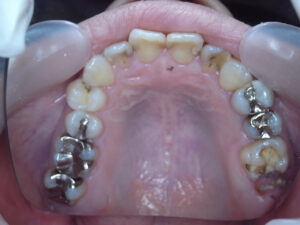

口腔内写真で明らかに違いが判るのは

保険で銀歯→ 自費で白い歯→

レントゲンでは神経の詰め物の状態の違い→